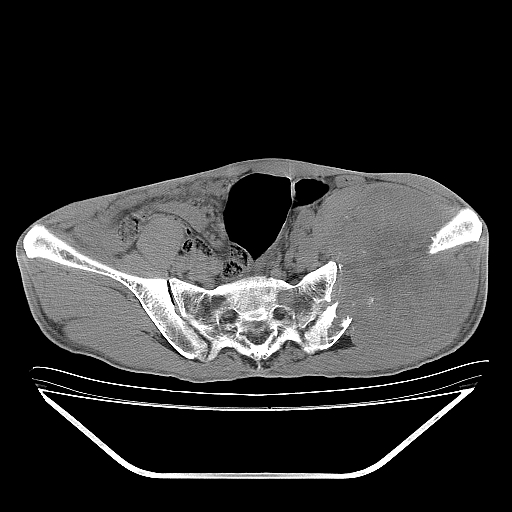

以下是引用天南地北在2007-10-4 18:01:00的发言:[br][br]考虑左髂部恶性肿瘤(溶骨性骨质破坏+软组织肿块影+残留骨质);以滑膜肉瘤可能性大。[br]建议穿刺活检

以下是引用liuyue在2007-10-4 23:38:00的发言:[br]左髂部恶性肿瘤,建议穿刺活检,或先做肺部检查,除外肺癌转移之可能。